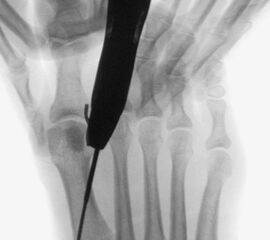

• Motorkonsole (RPM max. 6000 Touren bzw. weniger) (Abb. 2).

• Shannonfräse 12 mm Länge 2 mm Durchmesser (dorsale Osteotomie), Shannonfräse 8 mm Länge 2 mm Durchmesser (plantare Osteotomie).

• Spülflüssigkeit (Kontinuierliche Spülung entweder über die Konsole oder manuell).

Die Fräse wird auf eine Drehzahl von 3000 – 5000 RPM eingestellt.